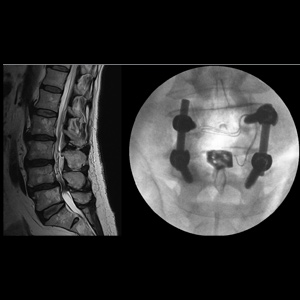

Spinal stenosis (Lumbar) Spinal stenosis (Cervical) Spinal stenosis (Thoracic) Lumbar Disc Herniation Spondylolisthesis Cervical Foraminal Stenosis Vertebroplasty Lumbar Fusion Anterior Cervical Fusion (ACDF) Posterior Cervical Fusion Thoracic Fusion Revision Lumbar Fusion Surgery Facet Joint Cyst Spinal Tumour Minimally Invasive Lumbar Fusion (XLIF) Minimally Invasive Lumbar Fusion (ALIF) Lumbar Fusion (TLIF) Thoraco-lumbar Fusion Lumbar Corpectomy Complex Lumbar Spine Surgery (Spino-pelvic fixation) Complex Cervical Spine Surgery Complex Thoracic Spine Surgery Occipito-cervical Fusion Minimally invasive surgery for thoracic disc herniation Other Related Topics